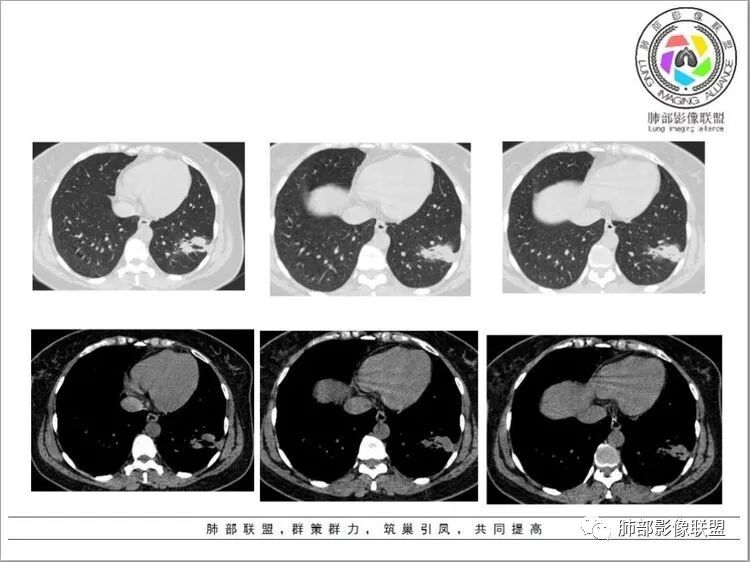

左肺上叶及下叶背段胸膜下磨玻璃结节,下叶叶间裂结节,叶间裂凹陷,下叶外基底段实变及磨玻璃影,支气管扩张,空洞,胸膜牵拉,首先考虑炎性,隐球菌?恶性病变待排

左肺下叶基底段不规则片状影,结节,磨玻璃,空泡,支气管进入,血管贴边,胸膜牵拉,考虑炎性病灶可能,隐球?鉴别结核

左肺下叶大片实变,周围可见小斑片及磨玻璃影,实变影部分边缘可见晕征,其内可见空泡及支气管扩张,考虑隐球。鉴别结核

中年女性,病史两月,炎性标志物不高。左肺下叶多发病灶,外外基底段见片状高密度影,边缘模糊,周围可见索条,内可见扩张支气管影。左肺上叶见小斑片伴GGO。考虑炎性病变,隐球?结核?

青中年女性,咳嗽,少量白痰,无伴胸痛,无发热。左肺下叶团片影,病灶较集中,多发蘑菇兄弟融合,病灶长轴平行胸膜,边缘收缩平直为主,有小空洞,小气泡,部分病灶周围有晕,支气管通畅,未见明显树芽,楔形征。考虑慢性炎,隐球菌?鉴别OP样病变,结核,粘液腺癌

胸部ct:左上叶小结节影,周围GGO边界不清。左下叶多发结节、斑片影、索条影,大病灶内可见小空洞,周围模糊晕,胸膜牵拉,支气管爬行征?考虑慢性炎性病变:结核?鉴别腺癌。

青年女性,丈夫有结核病史病程2月,胸部CT左肺上叶及下叶均有病灶,下叶外基底段实变及磨玻璃影,周围模糊,支气管扩张,空洞,胸膜牵拉,首先考虑炎性,隐球菌?

青年女性,咳嗽、咳痰2月,无发热,T-SPOT阳性,气管镜检查阴性,胸部CT:左肺多个病灶,下叶为主,有实变、结节、支气管扩张,空洞,内部密度不均,首先考虑炎性病变,T-SPOT阳性,NTM?。

青年女性,左肺多发斑片,结节病灶,密度不均,病灶边界不清,形态不规则,有支气管引流,边缘有磨玻璃影。综合分析,丈夫有肺结核病史,实验室TSPOT阳性。支持炎性,考虑结核,NTM,鉴别淋巴瘤。

2.左肺下叶胸膜下团片影及多发小片影,团片影长轴与胸膜平行,周围有模糊的晕,局部平直收缩,支气管近端堵塞,病灶内可见小空洞,空洞内壁光整,邻近胸膜牵拉。

结合肿块周围有多发小片、结节影等类似形态的卫星灶,病灶像炎性,没有游走性,但长时间段抗炎治疗无效,应当想到特殊感染的可能,如隐球菌感染或其他慢性炎症,如结核等。